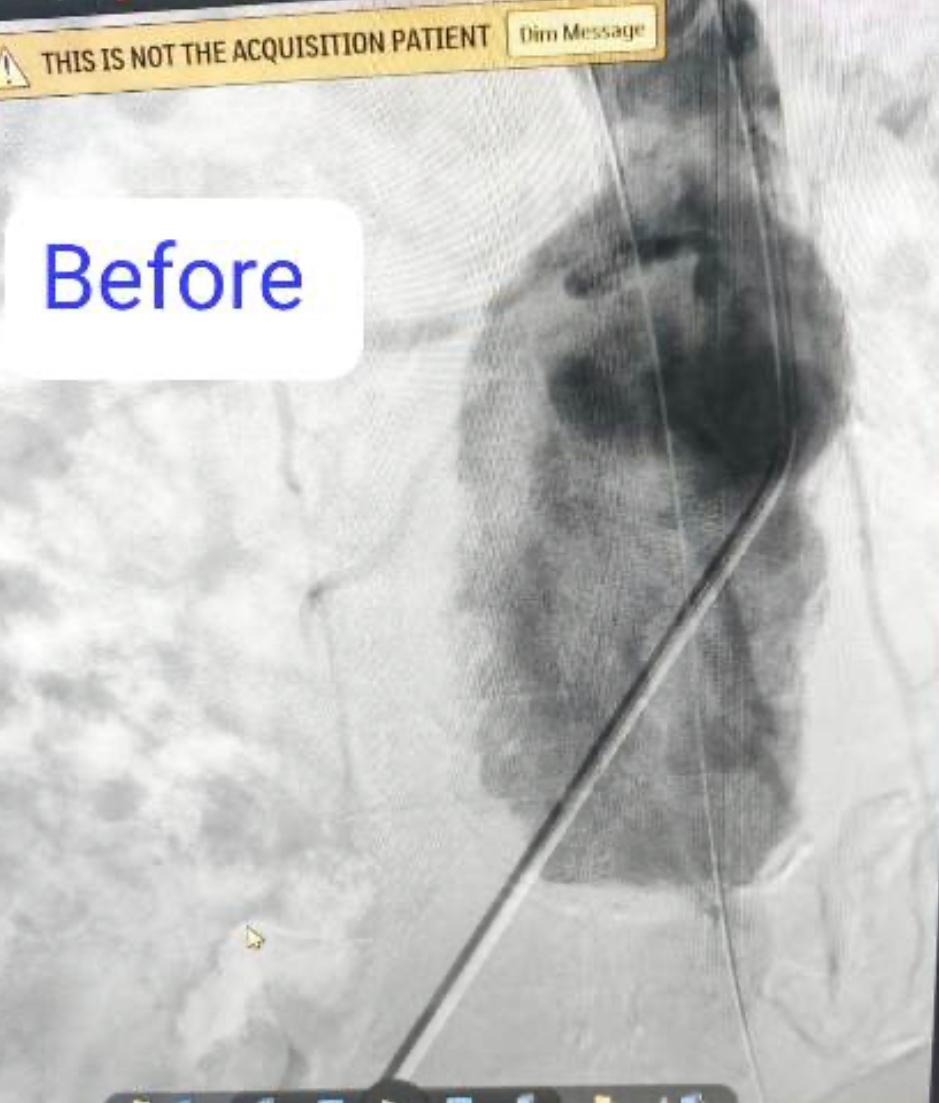

نجح فريق بقسم جراحة الأوعية الدموية بـ مستشفى بدر التابعة لكلية الطب جامعة حلوان، في إجراء تركيب قسطرة دقيقة جدًا لمريض يعاني من تمدد كبير في الشريان الأورطي والشريان الحرقفي الأيمن، حيث تم تثبيت دعامات مغطاة على هذين الشريانين لمنع انفجارهما، مما ساهم في إنقاذ حياته.